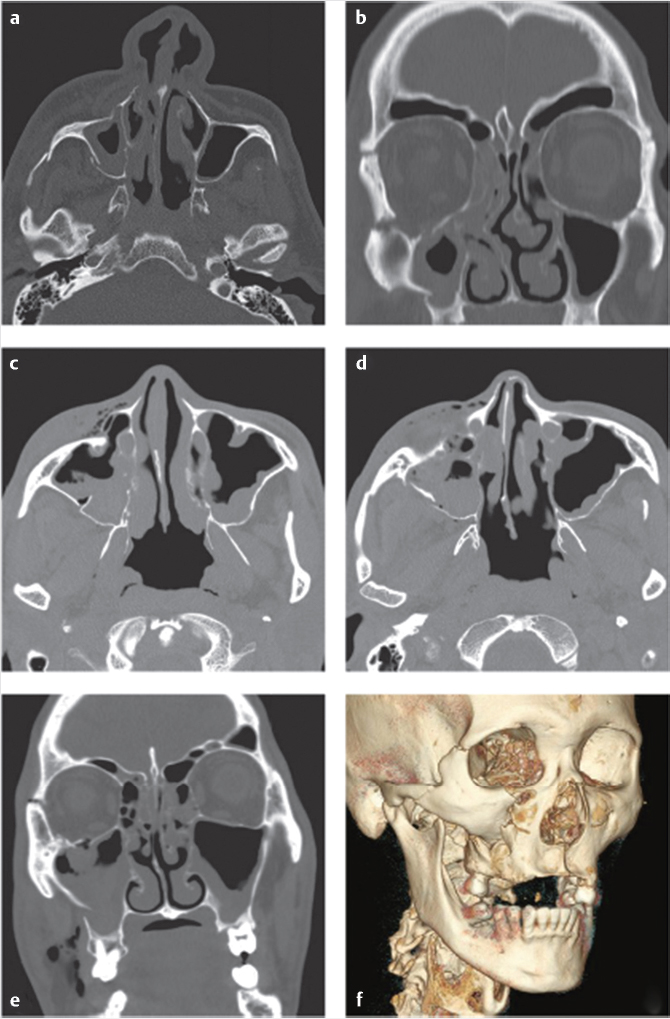

The medial canthal tendon (MCT) divides into anterior and posterior limbs which attach anteriorly along the anterior lacrimal crest and posteriorly along the posterior lacrimal crest. The MCT envelopes the lacrimal sac. The classification developed by Markowitz et al evaluated the MCT attachment and degree of comminution of the NOE fragment. 9 In type 1 fractures, the MCT remains attached to a large bony segment (central fragment) without comminution. In type 2 fractures, the NOE segment is comminuted with the MCT remaining attached to the central fragment. In type 3 fractures, there is comminution of the NOE segment with detachment of the MCT. A type 1 fracture is typically discernable from a type 2 or 3 fracture radiographically. MCT avulsion is generally determined intraoperatively making preoperative diagnosis of a type 2 versus type 3 fracture difficult (Fig. 19‑2).

The transnasal canthopexy is the most difficult aspect of NOE repair. Fortunately, only 3% of patients require canthopexy. The MCT may be posteriorly approached through the coronal approach or anteriorly with a small incision through dermis 3mm to the medial canthus. There are multiple techniques to anchor the MCT to a point of attachment (transnasal wire, plate, screw). Regardless of the technique, the point of attachment should be located superior and posterior to the posterior lacrimal crest. Primary repair of the nasolacrimal apparatus is controversial and beyond the scope of this text (Fig. 19‑3).